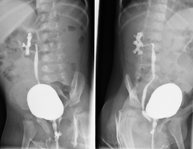

La urografia intravenosa (UIV) consisteix en l'obtenció d'imatges radiològiques seriades del ronyó, vies urinàries i bufeta. Aquest estudi requereix sempre l'ús d'un contrast iodat. - Cistografía (CUMS)

La cistouerotrografia miccional seriada consisteix en l'obtenció d'imatges radiològiques per valorar l'anatomia i la funció de la uretra i la bufeta amb l'administració de contrast iodat a través d'una sonda vesical. - Uretrocistografia (Uretro-Cums)

- Cystography

Serial voiding cystourethrography involves radiological imaging to assess the anatomy and function of the urethra and bladder with the administration of iodinated contrast through a bladder catheter.